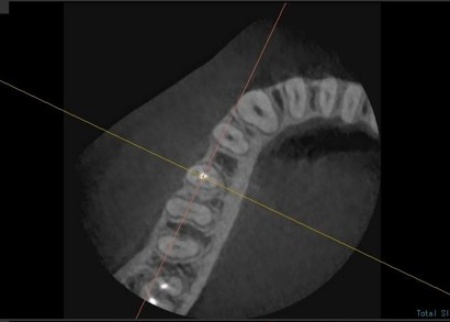

拝見したところ、右下奥歯(第2小臼歯)には保険診療の白い被せ物であるCAD/CAM冠が装着されていましたが、破折して外れている状態でした。

右下奥歯を詳しく検査をした結果、過去に細菌感染した神経を取り除いてから薬を詰める「根管治療」が行われていることがわかりました。

ただ、その手前の右下奥歯(第1小臼歯)では、歯の内部に細菌が侵入して炎症が生じており、歯根の先に膿が溜まる根尖(こんせん)病巣を発症しています。

まず、血液や唾液に含まれる細菌が根管内に入るのを防ぐため、ゴム製のシートであるラバーダムで患部周辺を覆って治療部位だけを露出させ、マイクロスコープで確認しながら感染部位を丁寧に除去しました。

根管内が清潔になったら、再び細菌が入り込まないようにしっかりと薬を詰めて封鎖後、レントゲン撮影で根尖病巣の治癒を確認しました。